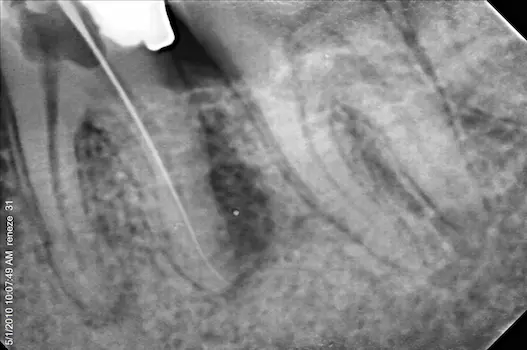

A Root Canal Treatment is conducted by a Root Canal Specialist, Also known as an Endodontist when a patient comes in with a decayed or damaged tooth that might be infected. It is advisable to go through with the procedure rather than extracting the tooth as retaining natural teeth is always better than getting a false one after an extraction and not replacing teeth after extraction can affect the health of the remaining teeth. The soft inner chamber of the tooth known as the pulp –contains Nerves, Blood vessels and Connective tissue. When the pulp gets damaged or infected due to a chip in the tooth or dental decay that allows bacteria to enter, A Root Canal procedure needs to be performed in order to remove the infected pulp and clean and seal the inside of the tooth.

The duration of a Root Canal Procedure varies depending upon the severity of infection. Some Root Canal Treatment can be completed in a single sitting and are known as Single Visit Root Canal Treatment however, If the tooth is badly infected it might involve multiple sittings as your Endodontist has to ensure that all the infection has healed prior to filling the tooth.